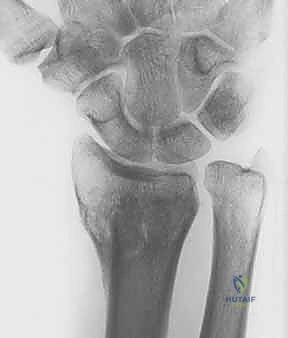

- الأشعة السينية الرقمية (X-rays): للرسغين السليم والمصاب، لمقارنة الزوايا وحساب مقدار التشوه بدقة.

- الأشعة المقطعية (CT Scan) مع إعادة البناء ثلاثي الأبعاد (3D Reconstruction): هذه الخطوة حاسمة. تتيح للدكتور هطيف رؤية العظم من جميع الزوايا، وتحديد مكان القص بدقة متناهية.